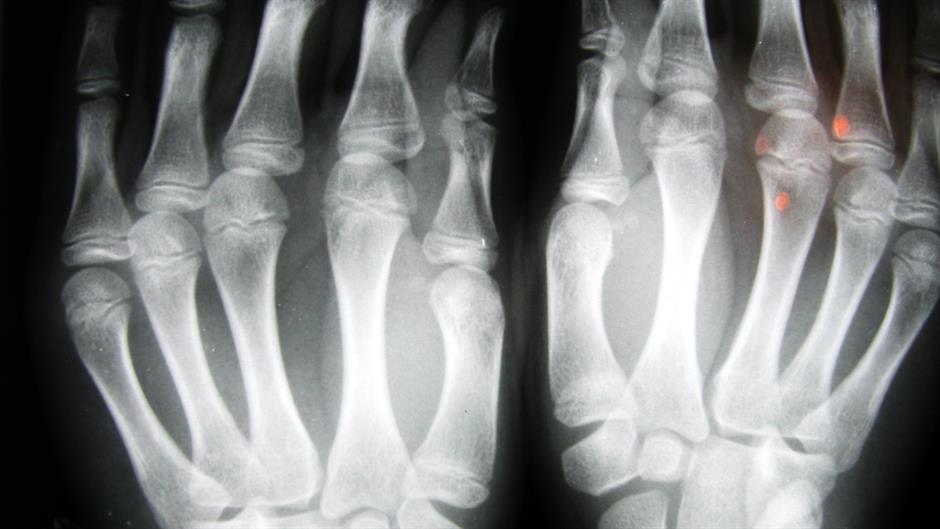

Injekcije stanica vlastitog masnog tkiva u zglobove mogu ublažiti simptome osteoartritisa, bolne degenerativne bolesti koja vodi u invalidnost, utvrdili su češki znanstvenici.

Njihovo istraživanje pokazalo je da injekcija stanica iz masnog tkiva trbuha pacijenata u koljenski i druge zglobove ublažava čak do 75 posto simptome kod gotovo dvije trećine pacijenata.

Pacijenti su praćeni između 12 i 54 mjeseca nakon injekcije. U najvećem broju slučajeva injekcije su davane u zglobove koljena i kuka a kod nekih pacijenata istovremeno je tretirano i više zglobova.